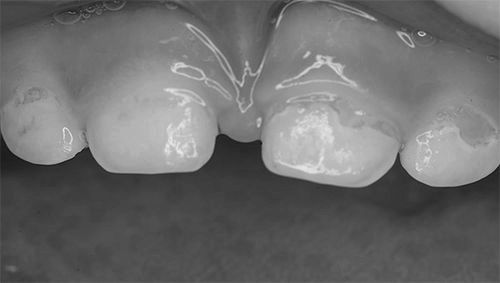

- зміна однорідності кольору емалі і поява білих плям (як при флюорозе),

Початкова форма виглядають у вигляді білястих плям і смуг на поверхні емалі і ця поверхня стає шорсткою, втрачає природний блиск, набуваючи Меловідниє плями. Убутку тканини зуба на цьому етапі ще не відбувається.

Поверхнева форма характеризується руйнуванням зуба до емалевої межі. Залежно від індивідуальної чутливості дитини, скарги на больові відчуття можуть бути відсутні. Емаль набуває відтінок, який варіює від світло-коричневого до чорного.